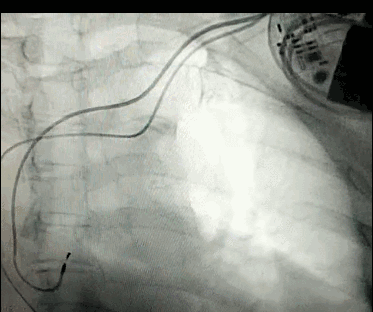

腦血管成像的“金標(biāo)準(zhǔn)”!——DSA三部曲之技術(shù)篇

DSA是將造影劑注入需要檢查的血管中,使血管顯露原形,然后通過系統(tǒng)處理,使血管顯示更加清晰,便于醫(yī)生診斷或進(jìn)行手術(shù)。

淺析DSA的前世今生!

數(shù)字減影血管造影術(shù)是醫(yī)學(xué)影象學(xué)中,繼X線CT之后的又一項(xiàng)新技術(shù),也是當(dāng)前醫(yī)學(xué)影象學(xué)中具有突破性的重大進(jìn)展。?